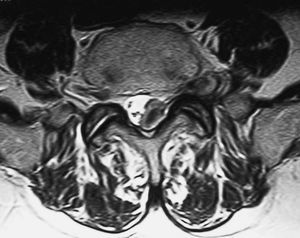

Fig. 3.--RM secuencia SE pT1. Corte axial. Lesión en canal, foramina y espacio extraforaminal isointensa con respecto al músculo.

Varón de 77 años con lumbociatalgia izquierda de tres meses de evolución. Se practica tomografía computarizada (TC) y resonancia magnética (RM) de columna lumbar.